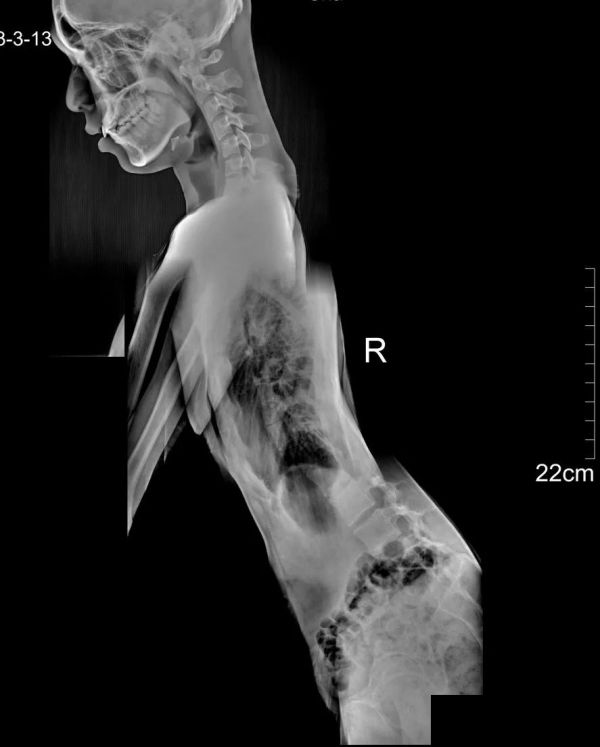

檢查項(xiàng)目:EOS全身正側(cè)位

影像所見(jiàn)

胸7、11、12蝴蝶椎體畸形,胸6-8椎間隙、胸10-11椎間隙顯著變窄。脊柱側(cè)彎,胸椎以胸9為中心向右側(cè)彎,Cobb角約20°;腰椎以腰3椎體為中心向左側(cè)彎,Cobb角約28°。胸腰段脊椎前凸。

測(cè)量參數(shù)如下:胸椎后凸角 (TK:T1/T12)約11°,腰椎前凸角 《LL:L1/S1) 約17°,矢狀面軸向距離 (SVA) 7mm,骨盆入射角 (FI)約47°。

雙側(cè)下肢長(zhǎng)度測(cè)量如下:右側(cè)股骨頭中心至脛骨 下穹隆長(zhǎng)度約829mm,左側(cè)長(zhǎng)度約820mm。左側(cè)膝關(guān)節(jié)中心向外偏離Mikulicz線10mm。

影像結(jié)果

胸7、11、12蝴蝶椎體畸形,胸6-8、胸10-11阻滯椎,脊椎側(cè)彎;左膝關(guān)節(jié)內(nèi)翻。